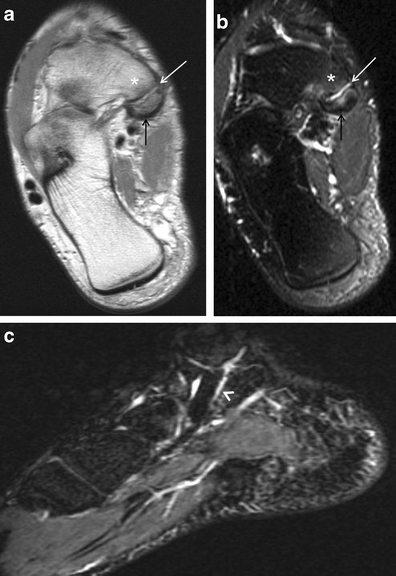

Bony sesamoiditis in a patient with plantar forefoot pain. Short axis PD (a) and T2-weighted fat-saturated (b) images reveal a mild asymmetric pattern of bone marrow oedema confined to the medial hallucal sesamoid. Note lack of oedema in the lateral hallucal sesamoid, first metatarsal head and surrounding soft tissues. Oblique sesamoid radiograph (c) shows no discernible abnormality. These results suggest bony sesamoiditis or stress reaction

Osteonecrosis. a Short-axis and sagittal CT images depict a fragmented medial hallucal sesamoid (black arrows), with increased density of the fragments (white arrows) which suggests post-traumatic osteonecrosis. b Short-axis and sagittal T2-weighted fat-saturated MRIs, and sagittal T1-weighted MRI obtained 1 month later show a pattern of severe bone marrow oedema (white arrows) with T1 hypointensity (black arrow) isolated to the medial hallucal sesamoid, and further collapse of the medial hallucal sesamoid, consistent with progression of osteonecrosis. Note normal marrow signal in the first metatarsal head (asterisks)